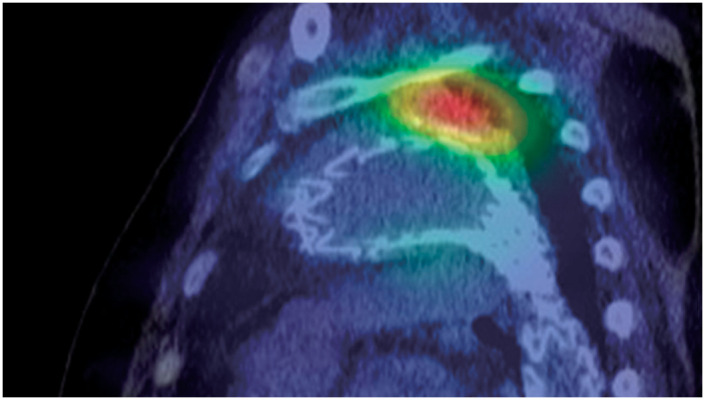

一位79岁的男性因膀胱癌经尿道切除而入院。2年前曾因Stanford B型急性主动脉夹层和胸主动脉瘤行胸血管内主动脉修复术。在住院期间,计算机断层扫描结果提出了支架移植感染的怀疑。血培养证实存在溶胆链球菌。pasteurianus。镓显像支持支架感染的诊断。随后的下消化道内窥镜检查显示下直肠结直肠癌。然后我们对支架感染进行手术治疗。

A 79-year-old man was admitted for transurethral resection of a bladder cancer. He had a history of thoracic endovascular aortic repair for Stanford type B acute aortic dissection and thoracic aortic aneurysm performed 2 years prior. During hospitalization, computed tomography scan findings raised suspicion of a stent-graft infection. Blood cultures confirmed the presence of Streptococcus gallolyticus ssp. pasteurianus. Gallium scintigraphy supported the diagnosis of a stent-graft infection. A subsequent lower gastrointestinal endoscopy revealed a colorectal cancer in the lower rectum. We then performed surgery for the stent-graft infection.